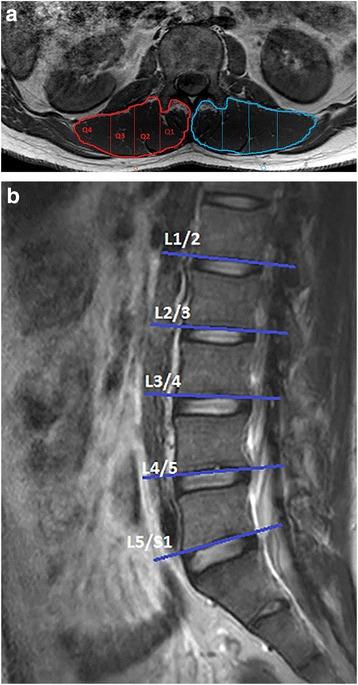

Axial 3-Tesla T1W MRIs from ten adult subjects (3W, 7M; mean age 52.8 ± SD 7.2 years) were randomly selected from the large prospective cross-sectional Hong Kong Population-based Disc Degeneration Cohort study examining lumbar spine degeneration. The selected sample included subjects with mixed imaging-determined disc degeneration and low back pain history. Two raters with MRI lumbar paravertebral muscle analysis experience (R1 > 250 h and R2 > 1000 h) repeat-measured the image-set a week apart. Multifidus and erector spinae (spinalis, longissimus and iliocostalis) were manually outlined together on a single-slice from the inferior vertebral end-plates of L1 to L5 using a semi-automated, quartile-defining (Q1-4 (medial to lateral) and Qmean) MatLab-based programme. Bland-Altman plots and intra-class correlation coefficients (ICC) with 95 % confidence intervals (CI) describe intra- and inter-rater reliability according to lumbar level, quartile, and side, and combined level and quartile.

从大型前瞻性横断面香港人群椎间盘退变队列研究中随机选取10名成年受试者(3名女性,7名男性;平均年龄52.8±标准差7.2岁)的轴向3特斯拉T1W MRI,该研究旨在研究腰椎退变情况。所选样本包括经影像学检查确定有椎间盘退变和腰痛病史的受试者。两名有MRI腰椎旁肌肉分析经验的评估者(R1>250小时,R2>1000小时),间隔一周对图像集进行重复测量。使用基于MatLab的半自动四分位数定义程序(Q1-4(从内侧到外侧)和Qmean),在L1至L5椎体下终板的单一层面上手动勾勒多裂肌和竖脊肌(棘肌、最长肌和髂肋肌)。Bland-Altman图和组内相关系数(ICC)以及95%置信区间(CI),根据腰椎水平、四分位数和左右侧,以及综合水平和四分位数来描述评估者内和评估者间的可靠性。